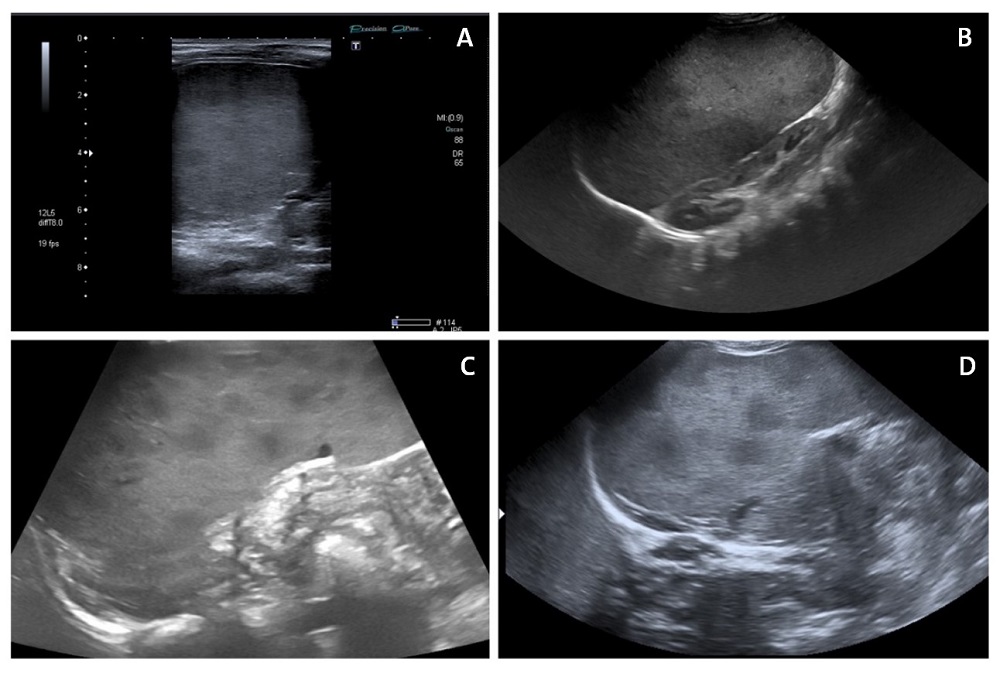

En todos ellos se realizó ecografía abdominal, donde se observó esplenomegalia, con presencia de múltiples lesiones nodulares hipoecoicas redondeadas subcentimétricas (Fig. 1). Estas tuvieron un tiempo de resolución variable.

Figura 1. A, C y D: esplenomegalia con múltiples lesiones hipoecoicas subcentimétricas compatibles con nódulos esplénicos. B: esplenomegalia masiva que aplasta al riñón

Figura 1. A, C y D: esplenomegalia con múltiples lesiones hipoecoicas subcentimétricas compatibles con nódulos esplénicos. B: esplenomegalia masiva que aplasta al riñón.